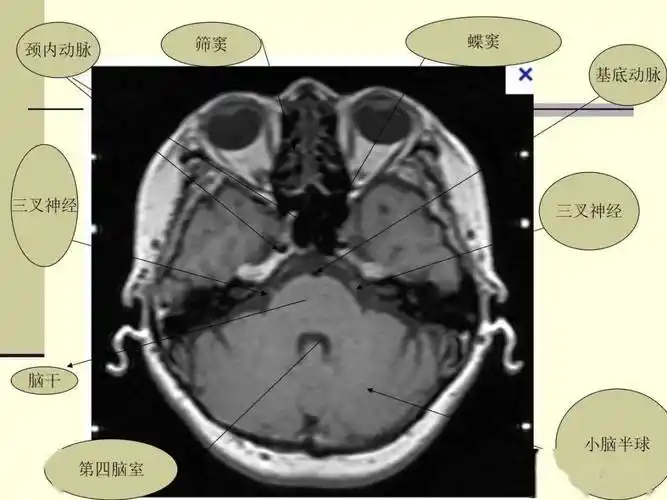

医学影像 #核磁图像#三叉神经 三叉神经分三支: 眼支(第 - 抖音

三叉神经解剖及常见疾病mr表现

共磁共振影像学检查对三叉神经痛诊断价值及外科微血管减压术mvd定位

磁共振检查全新升级(九)| 三叉神经颅外段磁共振成像

(图文)三叉神经痛的病因和治疗